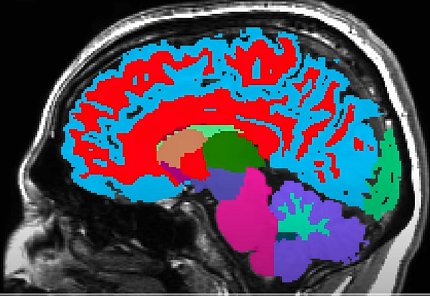

A brain scan, side view of brain, with different colors throughout brain regions

Researchers develop a tool to measure aging and predict future risk of dementia.

The team used MRI scans collected from participants in the Dunedin study. They used those images and their earlier data on declining function over time to develop a model for measuring aging rates from brain scans alone. They call their new measure, which uses 315 structural measures in the brain scans, Dunedin Pace of Aging Calculated from Neuroimaging (DunedinPACNI).